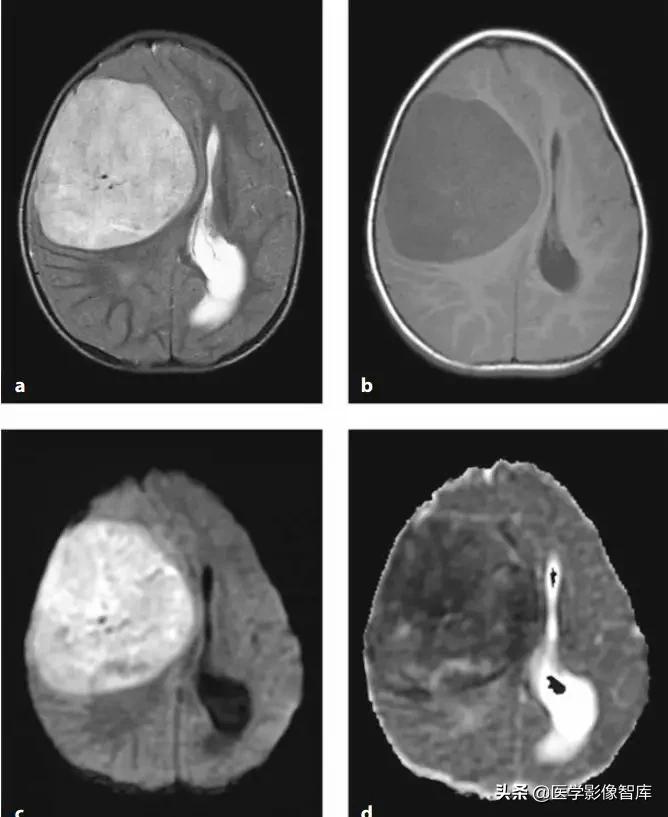

脑脓肿

我先放两张环形强化的图,大家可以猜猜哪个是脑脓肿,哪个是脑肿瘤。

图4 环形强化病灶对比

DWI是鉴别脑脓肿与高级别胶质瘤、转移瘤等良好手段。对于上图两个病例,其实加做一个DWI序列的话,就很好区分。左图患者DWI明显高信号,ADC图低信号,是脑脓肿;右图患者DWI低信号,ADC图高信号,是脑肿瘤。

图5 环形强化对比(脑脓肿 vs 胶质母细胞瘤)

脑脓肿主要是血源性感染,额、顶叶最常见,后颅窝小于15%,多位于灰白质交界处。一般为单发,多发少见(免疫抑制状态多见)。脓液表现为长T1长T2,FLAIR低信号,DWI高信号,ADC低信号;脓壁则包含了纤维成分,T1呈等/稍高信号,T2等/稍低信号,均匀环形强化(较光滑,深部薄,浅部厚);可以有子灶(卫星灶),破裂后形成小脓肿。

脑肿瘤

脑肿瘤的DWI信号主要取决于ADC值(细胞密度)与T2信号。低ADC值反应了高细胞密度和减少的细胞外间隙;高ADC值反应了低细胞密度,低细胞核浆比,细胞外基质增多(如图9)。高级别胶质瘤(包括间变性胶质瘤、间变性少突胶质细胞瘤、胶质母细胞瘤等)、淋巴瘤、转移瘤、髓母细胞瘤、中枢神经细胞瘤、原始神经外胚层肿瘤PNET等脑肿瘤,通常表现为DWI高信号、低ADC值。

相对ADC值:淋巴瘤<高级别胶质瘤<转移瘤。

对于胶质瘤而言,低级别的胶质瘤细胞密度稍低,其DWI呈等或稍高信号,高级别的胶质瘤则细胞密度较高,其DWI呈高信号,ADC值降低。这不是绝对的,因为DWI高信号还包含了T2信号,因此,有些肿瘤DWI高信号部分同时包含ADC低信号(弥散受限的部分)和等/高信号(T2投射效应的部分)。